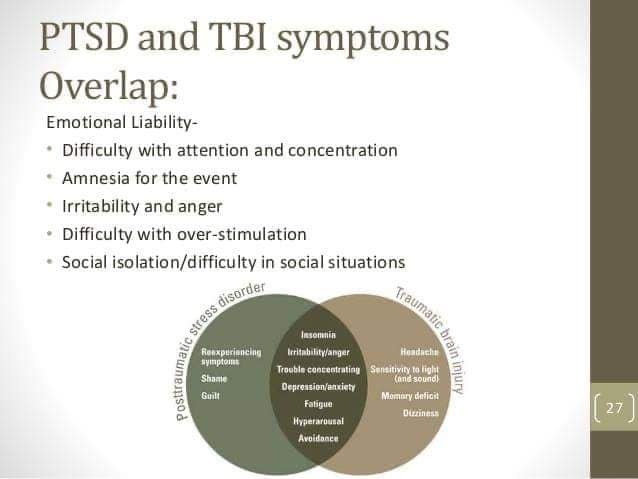

I have every single overlapping and social difficulty on the chart I sent.